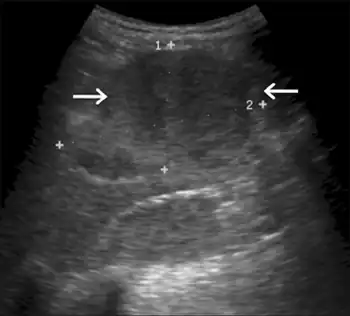

Gray-scale USG shows hepatomegaly with diffusely increased echogenicity and predominantly hypoechoic mass

The specific etiology of hepatic adenomas in GSD I remains unknown, despite ongoing research. The typical GSD I patient presenting with at least one adenoma is an adult, though lesions have been observed in patients as young as fourteen. Adenomas, composed of heterogeneous neoplasms, may occur individually or in multiples. Estimates on the rate of conversion of a hepatocellular adenoma into hepatocellular carcinoma in GSD I range from 0% to 11%, with the latter figure representing more recent research. One reason for the increasing estimate is the growing population of GSD I patients surviving into adulthood, when most adenomas develop.

Treatment standards dictate regular observation of the liver by MRI or CT scan to monitor for structural abnormalities. Hepatic adenomas may be misidentified as focal nodular hyperplasia in diagnostic imaging, though this condition is rare. However, hepatic adenomas in GSD I uniquely involve diffuse Mallory hyaline deposition, which is otherwise commonly observed in focal nodular hyperplasia. Unlike common hepatic adenomas related to oral contraception, hemorrhaging in GSD I patients is rare.

While the reason for the high prevalence of adenomas in GSD I is unclear, research since the 1970s has implicated serum glucagon as a potential driver. In studies, patients that have been put on a dietary regimen to keep blood sugar in a normal range spanning 72 to 108 mg/dL (4.0 to 6.0 mmol/L) have shown a decreased likelihood of developing adenomas. Moreover, patients with well controlled blood glucose have consistently seen a reduction in the size and number of hepatic adenomas, suggesting that adenomas may be caused by imbalances of hepatotropic agents like serum insulin and especially serum glucagon in the liver.[20]